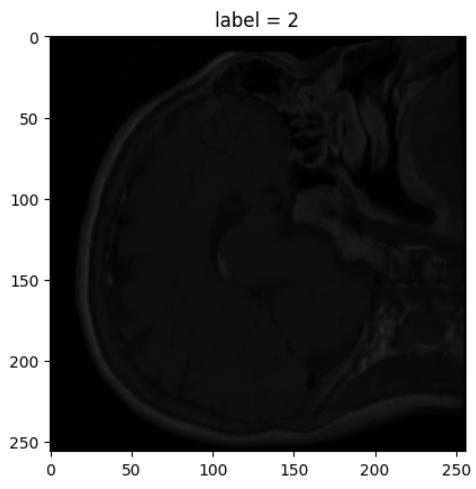

I have worked with various kinds of CNN networks including the inception network to classify medical images. An inception network offers more accuracy than previous types of CNN since its structure can avoid overfitting. To lower up the training costs of the models, transfer learning concept has been exploited in which CNN layers were pretrained with the large and infamous ImageNet dataset. The learning process is only applied to the fully connected layers that classify images.